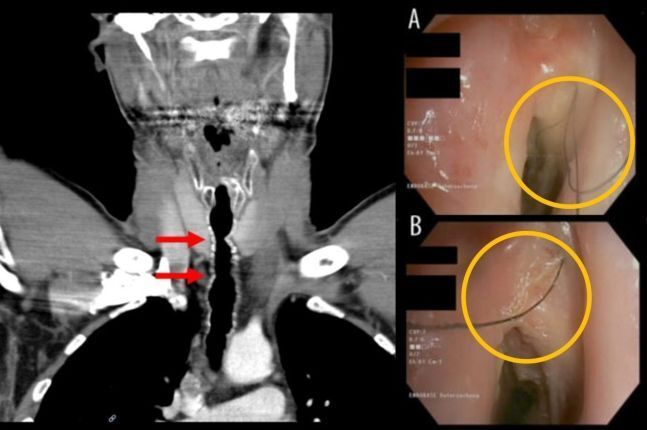

기관지 내시경 검사를 한 남성은 결과를 듣고 깜짝 놀랐다. 남성의 기도 안에 염증이 생기고 털이 나라고 있었다. A씨는 기관 내 모발 성장, 즉 목구멍에 모발이 자라는 진단을 받았다.

의료진은 A씨가 10살 때 익사할 뻔했고, 응급처치로 후두가 손상된 후 기관절개술을 받은 점에 주목했다. 당시 불규칙한 호흡을 규칙적으로 만드는 기관절개술을 받았다. 이후 귀의 피부와 연골을 자가 이식해 상처를 덮었는데, 이 부위에 털이 자란 것이다. 의사는 털을 뽑아 제거했지만 이후에도 털은 계속 자랐다.

A씨는 통증이 느껴질 때마다 병원을 찾아 털을 제거하는 치료를 받아야 했다. A씨의 목에는 약 5cm 털이 6~9개가 반복적으로 자라났고 일부는 성대를 지나 입으로 뻗어 나갔다. 이 털이 박테리아로 덮여 있었기 때문에 항생제 치료까지 받아야 했다.

털이 계속 자라는 문제는 A씨가 흡연을 중단한 2022년에야 해결됐다. 처음흡연을 한 지 30년 만이다. 의사들은 내시경 아르곤 플라즈마 응고술을 시행해 머리카락이 자라는 뿌리를 태웠다. 다음 해 두 번째 시술을 통해 모발이 자라는 현상이 완전히 사라졌다고 한다.